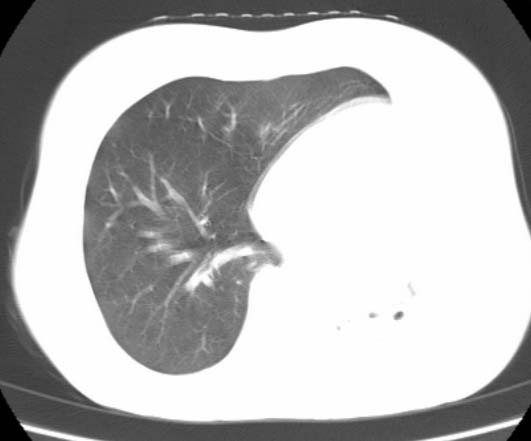

标题: CT25648:求教:是肺发育不全还是结核?

女  20岁。一月前咳血,诊“肺结核”抗痨治疗一月后,咳血停止,现复查。病人精神好。前后ct片对比未见明显变化。既往体检“正常”

1)考虑左肺结核并肺不张、支气管扩张。2)纵隔疝。

考虑左肺结核,左肺毁损,纵膈左偏,既往体检正常不可靠,tb一个月也不会这个样子的,有钙化,应该病程较长,冰冻三尺非一日之寒!

结核,左肺毁损。